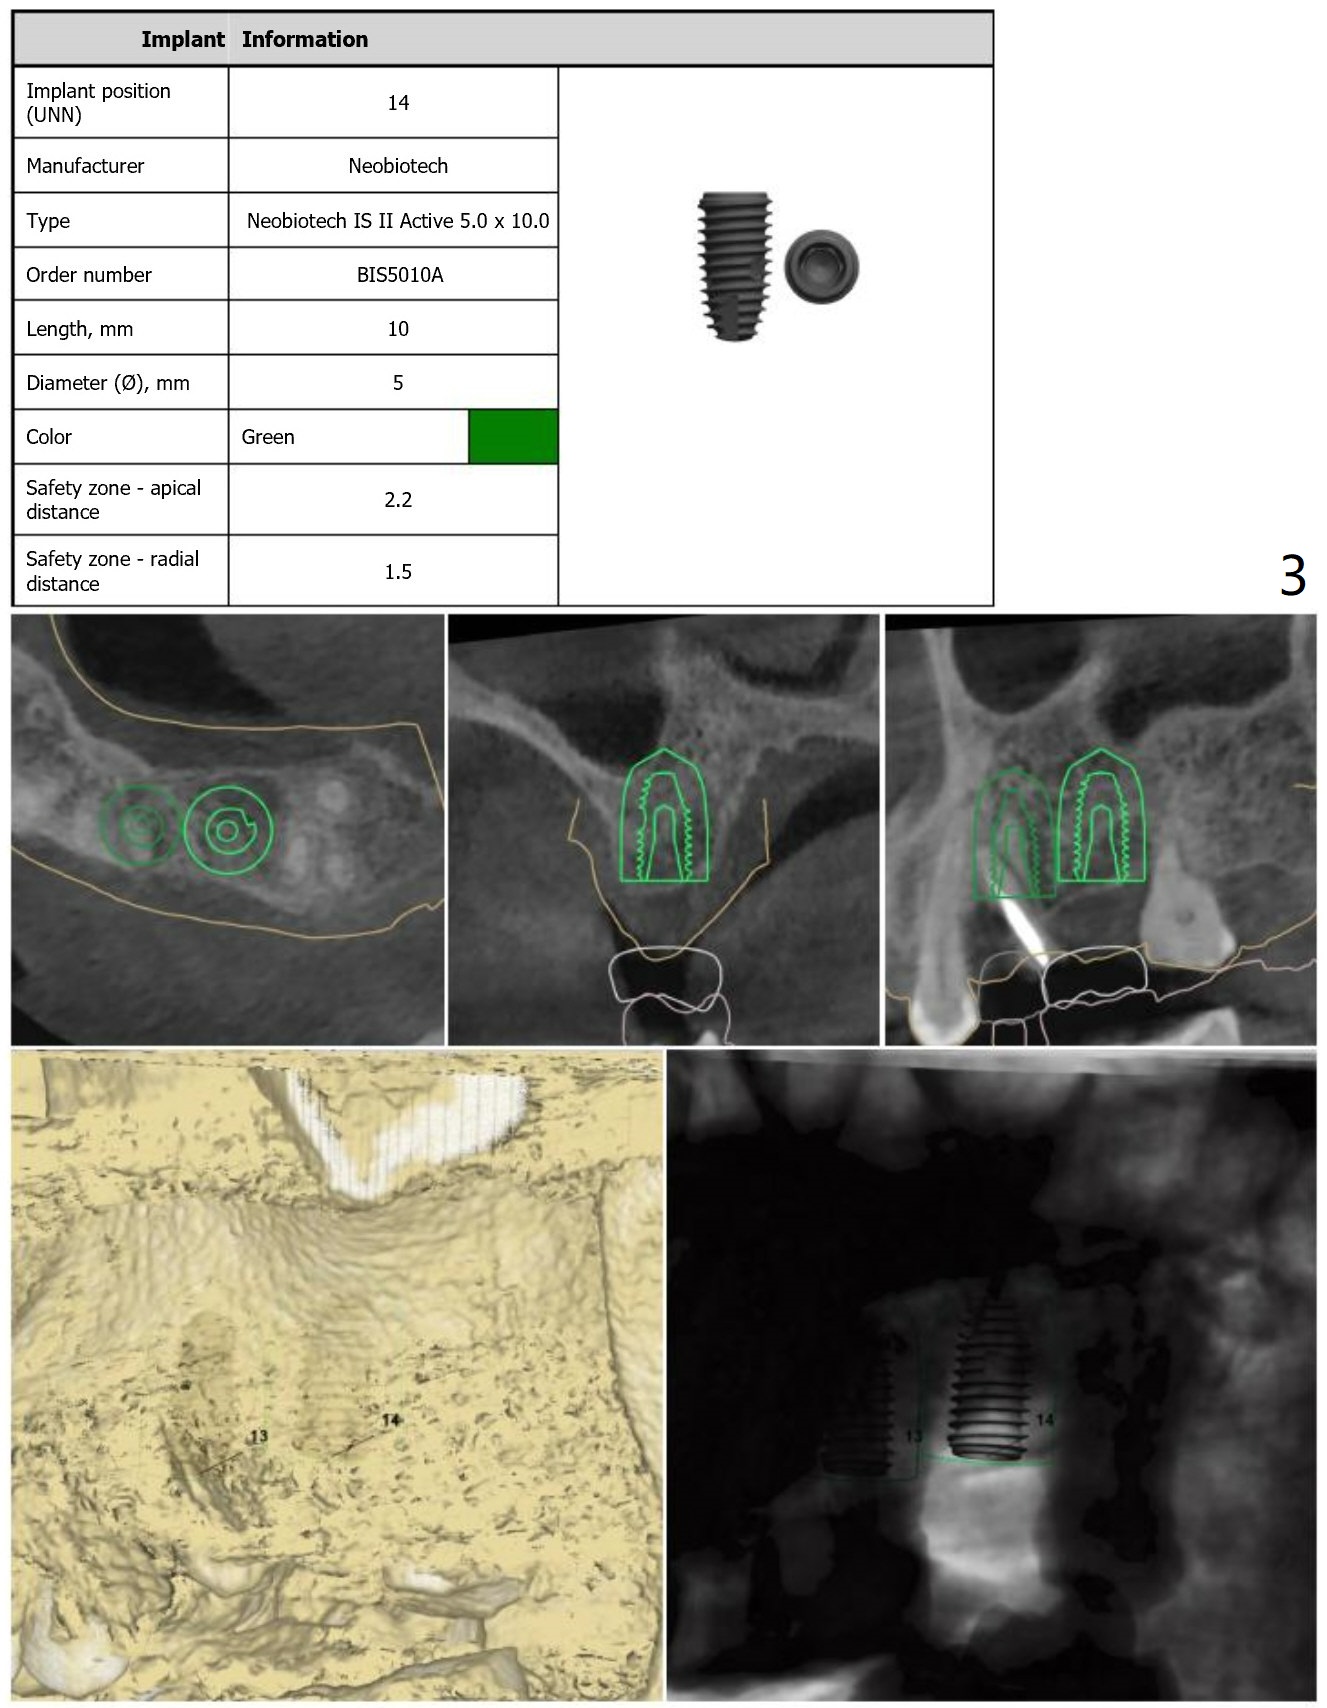

Guide for FPD

Return to Upper Molar Premolar Immediate Implant, Trajectory, Metronidazole